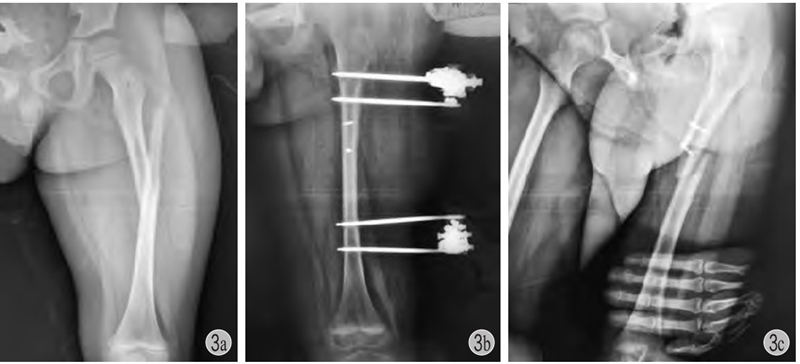

图3 患儿 男 7岁

a、b:左股骨干骨折,应尽量闭合复位应用弹性针或肌肉下接骨板固定,该患儿切开复位,局部螺钉+外架固定;c:拆除外架后3个月发生再骨折